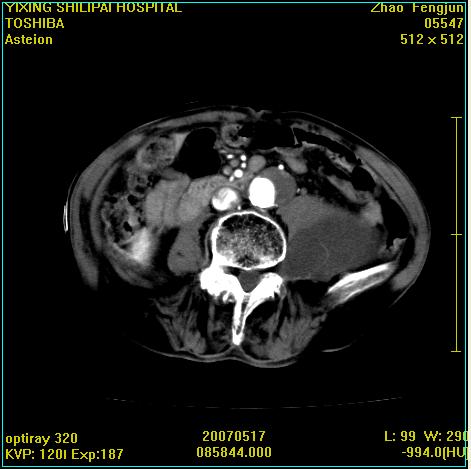

考虑:1、左侧腰大肌囊实性占位性病变(囊性神经根鞘瘤?);

2、右侧兰尾区囊性占位性病变(兰尾囊肿?囊腺癌?类癌?)

以下是引用xiaoniu在2007-5-26 10:45:00的发言:[br]腰大肌的病变应该没有问题,增强扫描还有轻度强化及细小血管影入内,应该排除脓肿,考虑占位性病变,腰大肌的占位多考虑:神经源性肿瘤。另外腹主动脉下端有真假腔的强化,考虑:主动脉夹层。[br][br][本贴已被 xiaoniu 于 2007-5-26 10:46:39 修改过]

以下是引用老爱克斯新网客在2007-5-26 18:26:00的发言:[br]1左下腹囊实性占位肿块,增强后不均匀强化,位于脊柱旁,椎体骨质无破坏软组织无肿胀,考虑神经源肿瘤神经鞘瘤可能大,2右下腹囊性占位性病变,增强后囊壁强化,考虑阑尾囊肿或囊腺瘤,